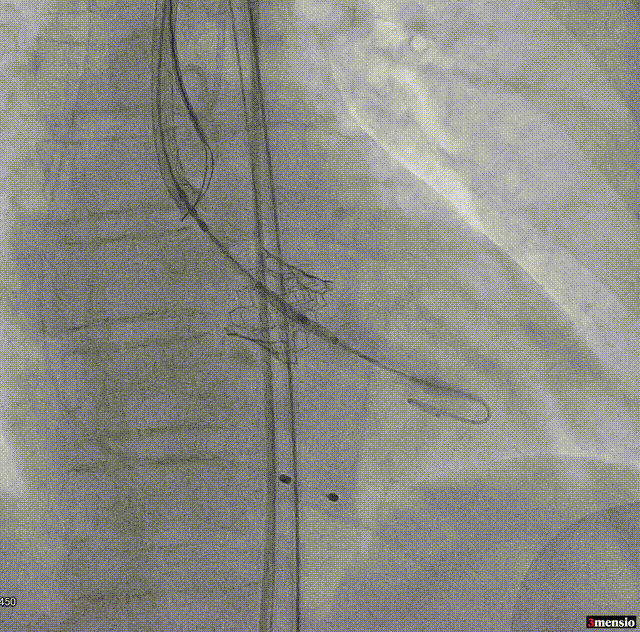

释放后腰迹明显,轻度瓣周漏,原体积后扩

根部造影显示微量瓣周漏

超声提示微量瓣周漏,瓣膜工作良好,最大跨瓣流速2.02m/s,平均压差6mmHg。

输送系统可调弯系统提高了过弓跨瓣的流畅度,术中团队配合默契,操作熟练,成功将瓣膜在最佳位置释放;输送系统进入到撤出仅耗时20分钟。术后即刻心超提示,瓣膜工作稳定,无反流,微量瓣周漏,植入效果理想。